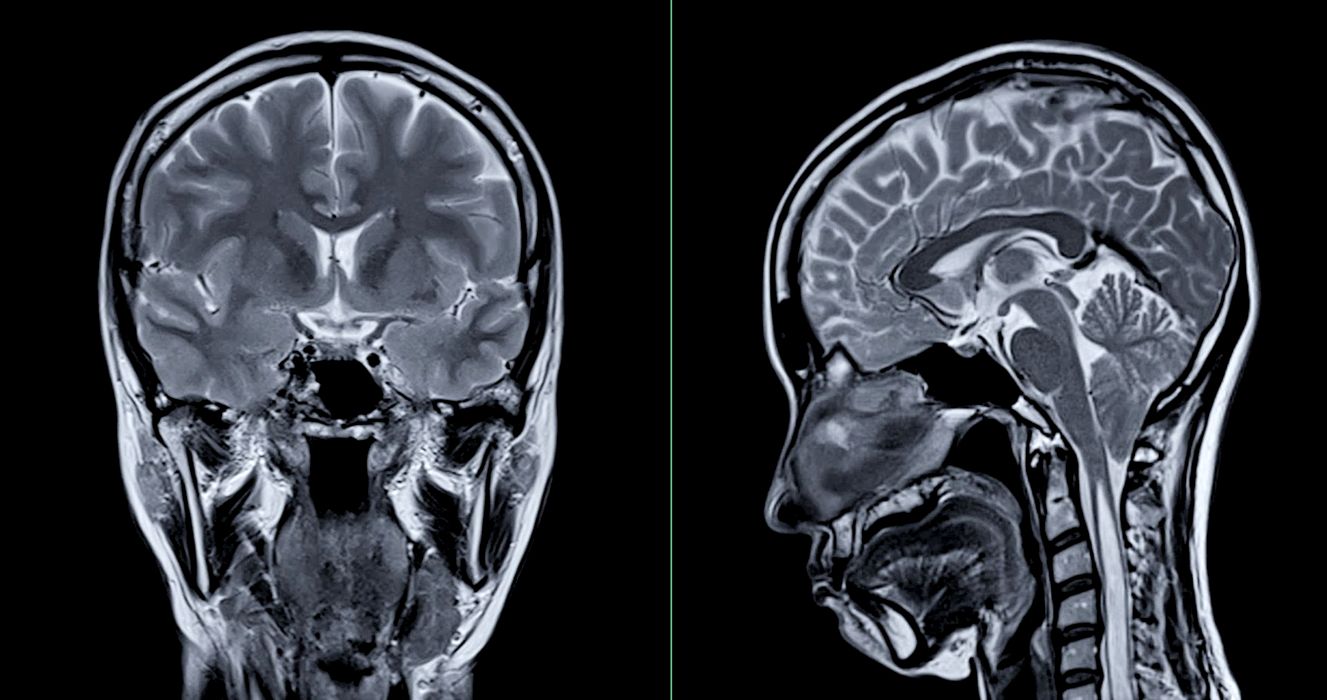

Ce s-a întâmplat după ce o femeie a auzit voci care îi spuneau că are o tumoare pe creier?

În 1984, o femeie perfect sănătoasă a început, brusc, să audă voci care îi spuneau că are o tumoare pe creier. Experiența a speriat-o profund, făcând-o să se teamă pentru sănătatea ei mintală, așa că […]